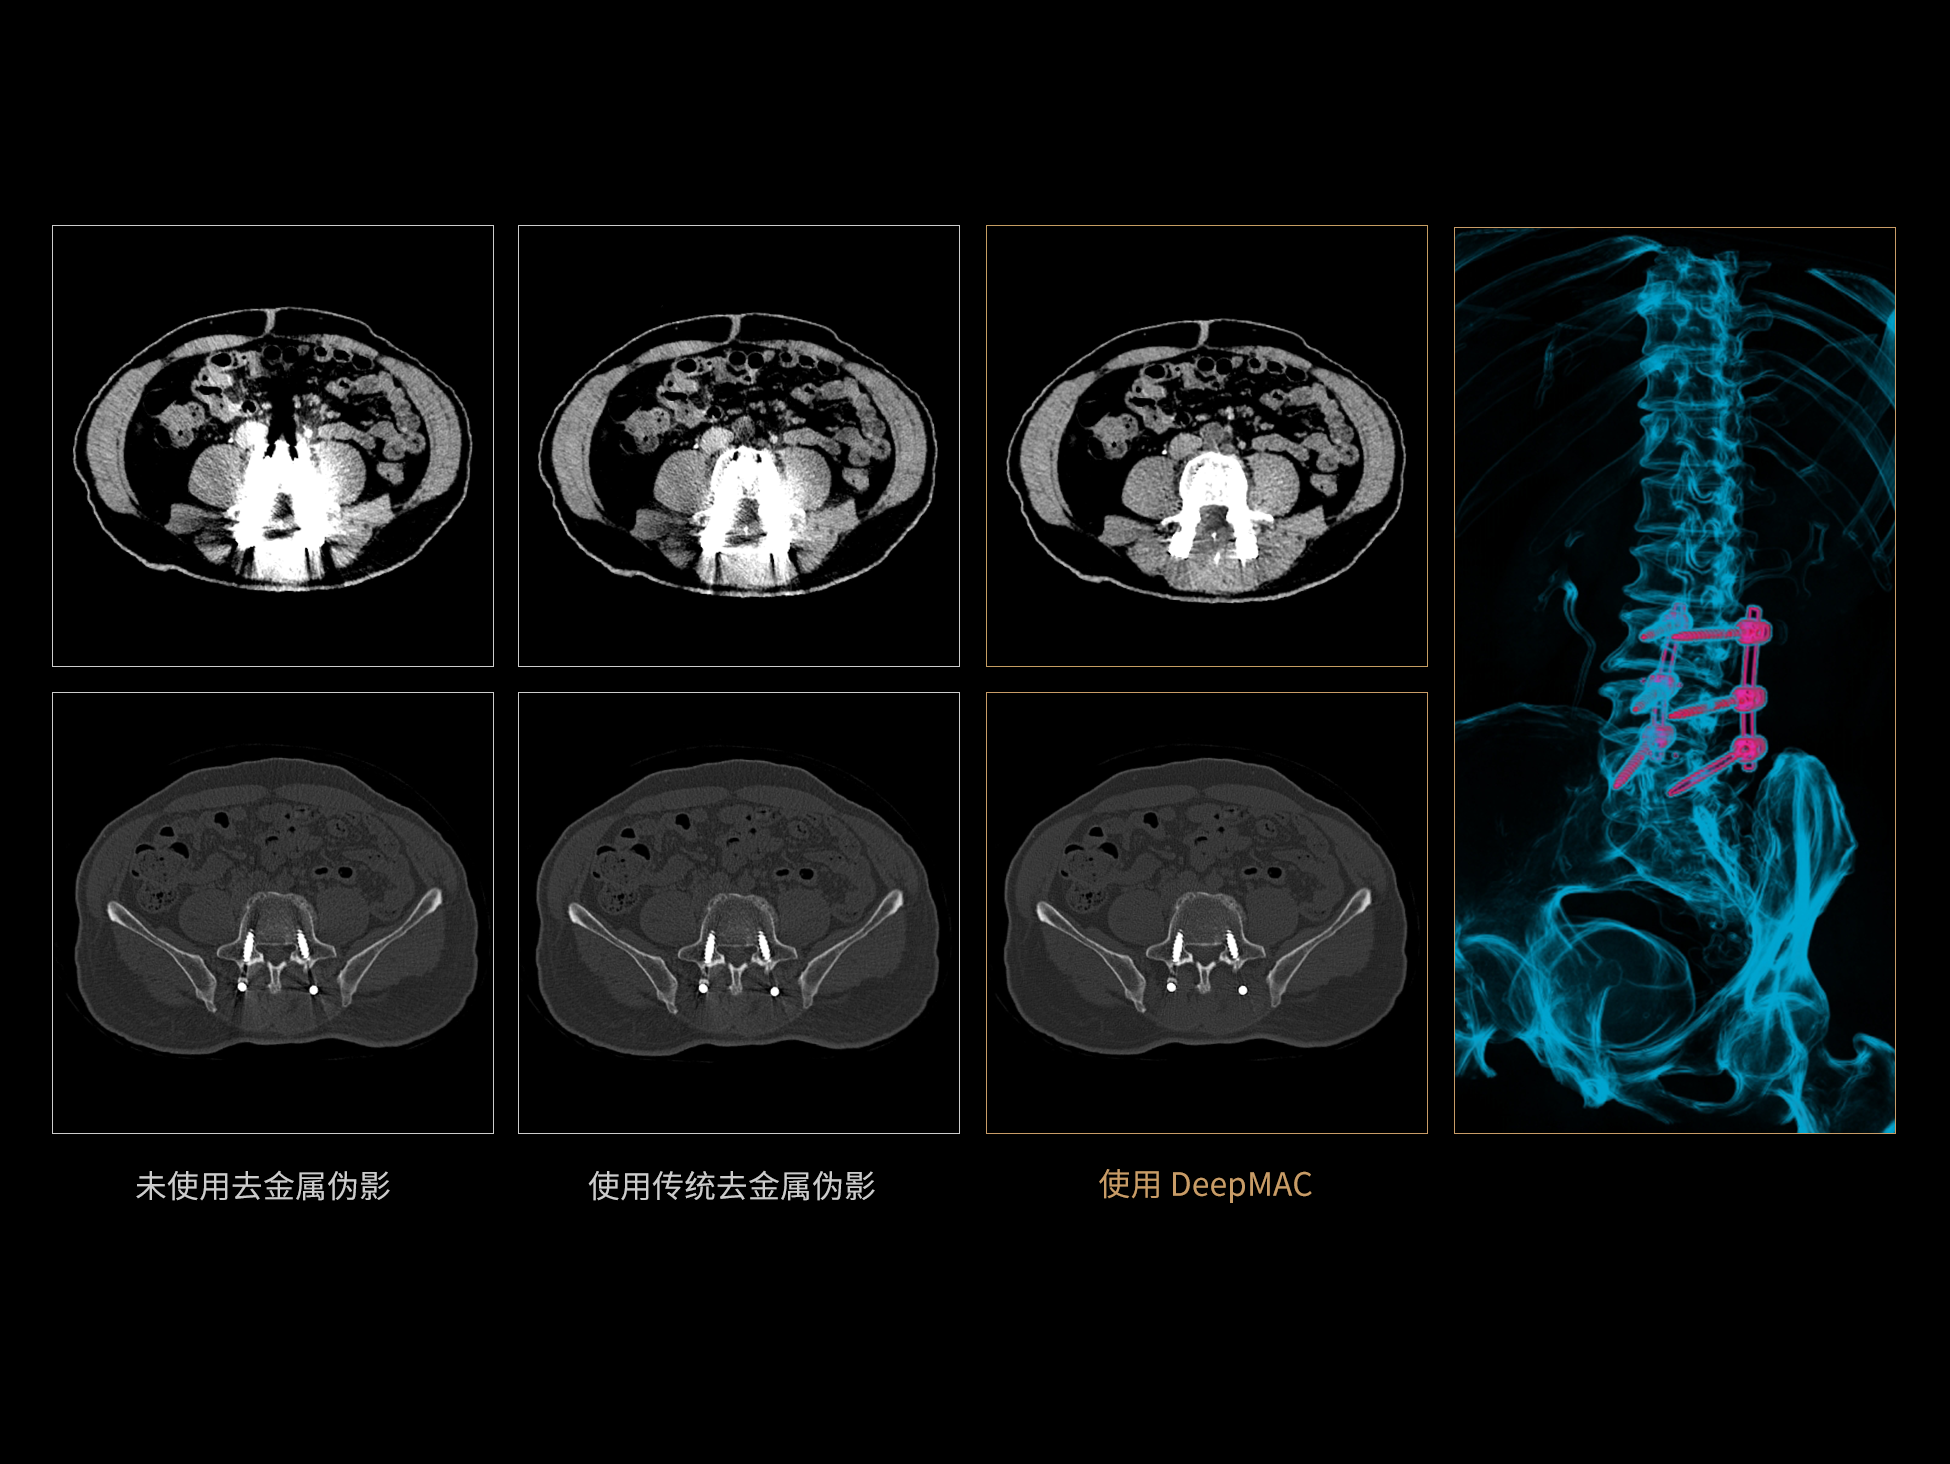

DeepMAC**:AI去金属伪影算法

DeepMAC**智能金属伪影校正技术通过深度学习算法有效解决了临床中各类不规则金属植入物导致的CT成像伪影问题,具备良好的通用性和稳定性。该技术依托大规模、高多样性的训练数据集,覆盖了包括髋关节置换体、脊柱内固定器(胸腰椎/颈椎)、四肢骨科植入物、牙科修复体以及血管介入弹簧圈等在内的金属植入物类型。通过深度神经网络的特征提取与解剖结构重建优化,DeepMAC** 在有效抑制金属伪影的同时,最大程度地保留了真实的解剖细节,显著提升了影像诊断的准确性。

±10HU

CT值准确性※ ※

≥50% 重建速度提升

相较传统算法,重建速度提高50%以上※ ※

** 仅供科研使用

※ ※数据在测试条件下,与传统MAC去金属伪影算法对比获得